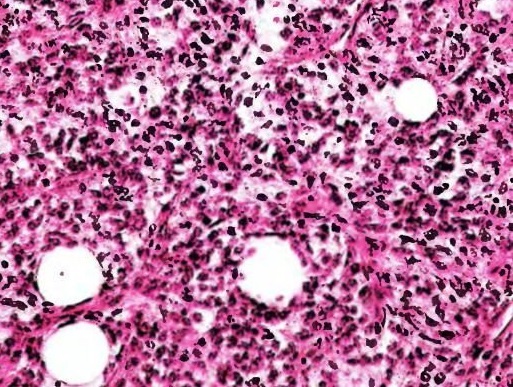

Гистологический препарат тканей липосаркомы